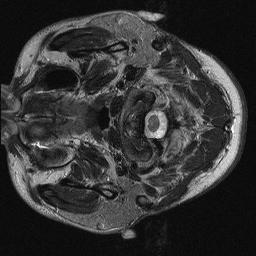

Magnetic resonance imaging serves as an essential tool for clinical diagnosis. However, it suffers from a long acquisition time. The utilization of deep learning, especially the deep generative models, offers aggressive acceleration and better reconstruction in magnetic resonance imaging. Nevertheless, learning the data distribution as prior knowledge and reconstructing the image from limited data remains challenging. In this work, we propose a novel Hankel-k-space generative model (HKGM), which can generate samples from a training set of as little as one k-space data. At the prior learning stage, we first construct a large Hankel matrix from k-space data, then extract multiple structured k-space patches from the large Hankel matrix to capture the internal distribution among different patches. Extracting patches from a Hankel matrix enables the generative model to be learned from redundant and low-rank data space. At the iterative reconstruction stage, it is observed that the desired solution obeys the learned prior knowledge. The intermediate reconstruction solution is updated by taking it as the input of the generative model. The updated result is then alternatively operated by imposing low-rank penalty on its Hankel matrix and data consistency con-strain on the measurement data. Experimental results confirmed that the internal statistics of patches within a single k-space data carry enough information for learning a powerful generative model and provide state-of-the-art reconstruction.